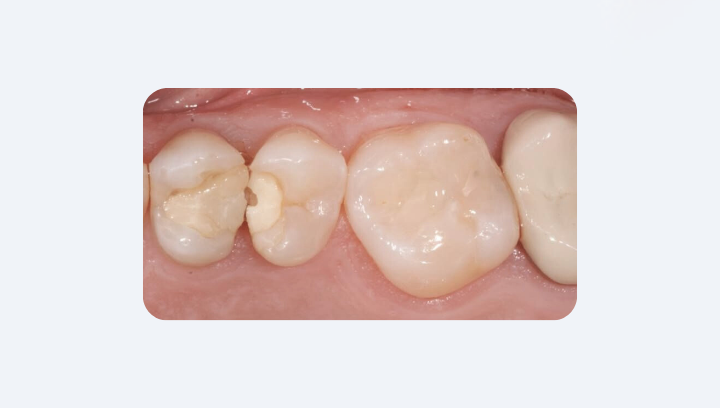

Видимые трещины, сколы или темная полоска вокруг пломбы

Часто первые проблемы с пломбой можно заметить собственными глазами. Достаточно внимательно присмотреться в зеркало при хорошем освещении. Если поверхность выглядит треснувшей или отколотой — это уже признак того, что пломба потеряла целостность. В таких микроповреждениях легко накапливаются остатки пищи и бактерии, а со временем они превращаются во входные ворота для вторичного кариеса.

Еще один тревожный сигнал — темная полоска по краю пломбы. Легкое общее потемнение светлых композитов со временем возможно, но четкая темная каемка означает, что под материал начали проникать пигменты и микроорганизмы. Это так называемая краевая микропроницаемость, и она всегда требует проверки у врача.

Даже если боль еще не появилась, любые видимые изменения — трещина, скол или темная каемка — означают, что пломба уже не герметична. В такой ситуации лучше не ждать симптомов, а сразу записаться к стоматологу: профилактическая замена реставрации значительно безопаснее, чем лечение запущенного кариеса или пульпита.